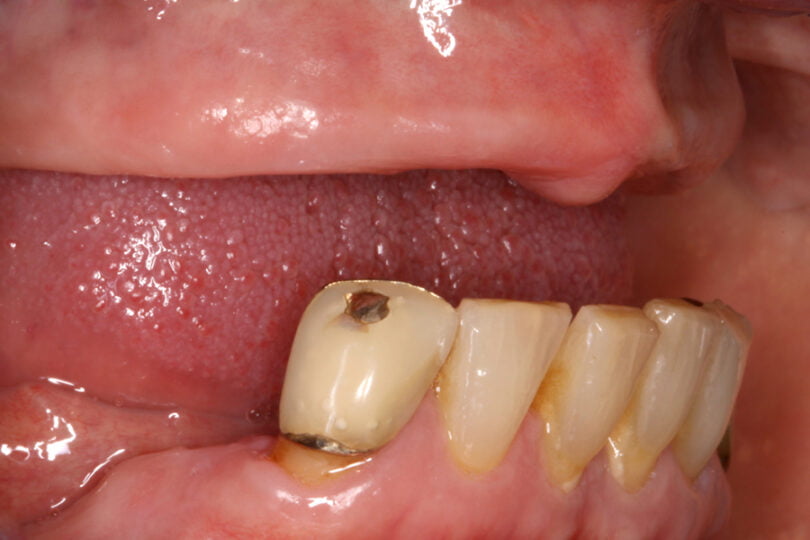

As seguintes imagens apresentam um dos casos incluídos no estudo (figura 03 – 15).